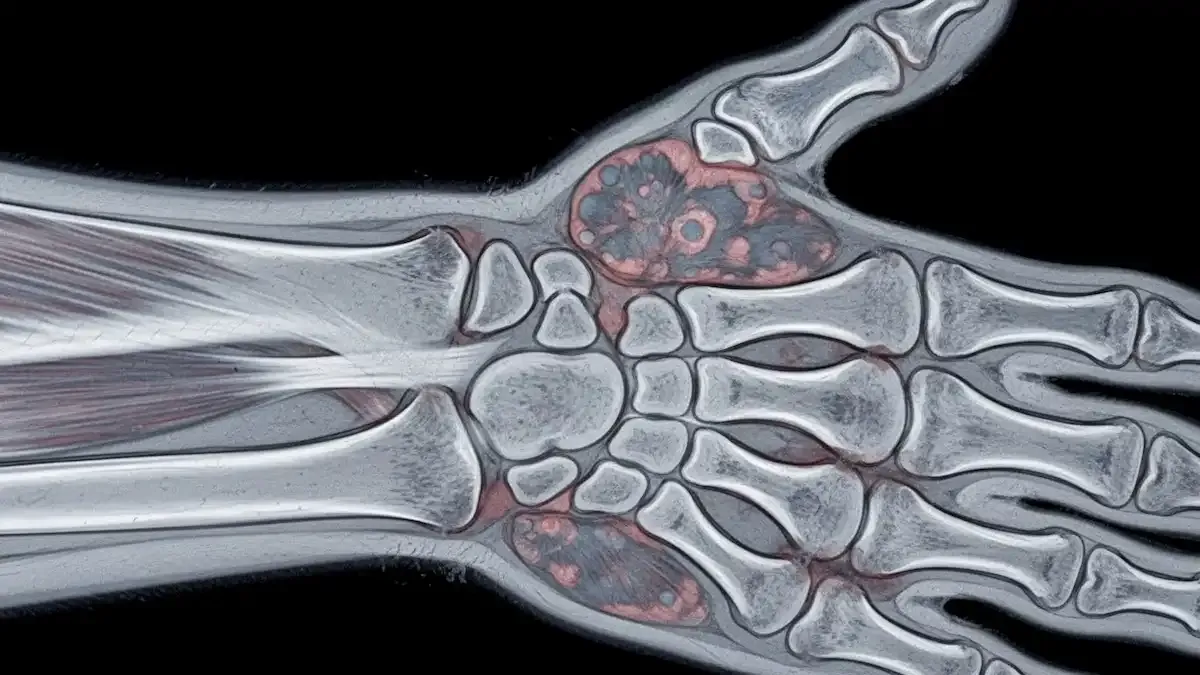

A escolha da técnica cirúrgica depende de diversos fatores, como o tempo de evolução, a localização da pseudoartrose e a presença de necrose avascular.

Quando há necrose avascular estabelecida, frequentemente opto pela técnica de Zaidemberg, utilizando enxerto ósseo pediculado do rádio distal.

Esta abordagem, que aperfeiçoei ao longo dos anos, permite preservar a vascularização do enxerto e oferece melhores chances de consolidação.